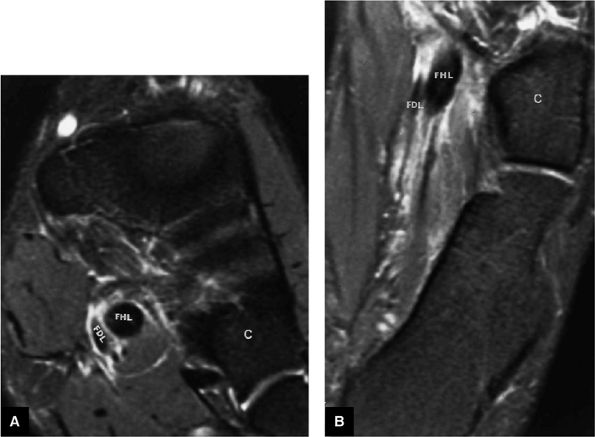

FIGURE 5.9 ● FLEXOR HALLUCIS LONGUS The flexor hallucis longus (FHL) flexes the great toe and plantarflexes the foot. The FHL is susceptible to injury during extremes of ankle plantarflexion and metatarsophalangeal dorsiflexion. The proximal sheath, 10 to 12 cm in length, has no mesotenon and may communicate with both the ankle joint and the sheaths of the flexor digitorum longus and tibialis posterior.